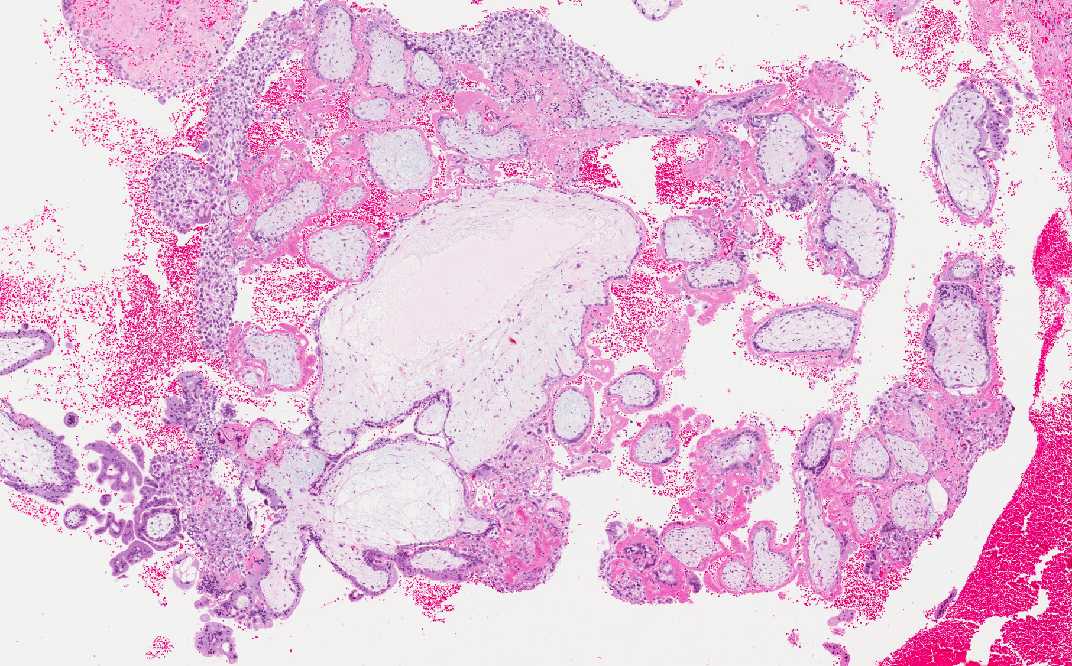

• Trophoblastic villi are noted in Area 1 but no fetal tissue is noted. Trophoblastic villi are far more common to be found than fetal tissues in these cases. Note the multinucleated syncytiotrophoblasts (arrow).

Area 1: The trophoblastic villi are illustrated here. Note the syncytiotrophoblasts (arrow).